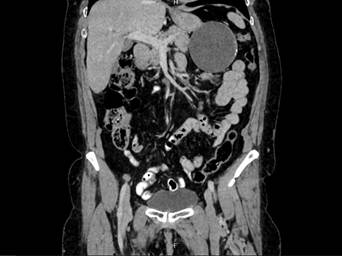

Se realizó una ecografía de abdomen total que informó una imagen quística de 8 x 7 cm, en íntimo contacto con la cola del páncreas. Posteriormente una tomografía computarizada de abdomen con contraste reportó una lesión hipodensa de aspecto quístico, de 86,6 x 78,5 mm, en contacto con la curvatura mayor del estómago, el cuerpo y la cola del páncreas, con paredes irregularmente engrosadas y calcificaciones periféricas aisladas en su interior. Como primera posibilidad se sugirió un tumor del estroma gastrointestinal (GIST, por sus siglas en inglés) (figuras 1 y 2). La endoscopia de vías digestivas altas diagnosticó una gastropatía antrocorporal no erosiva sin hallazgos patológicos adicionales.